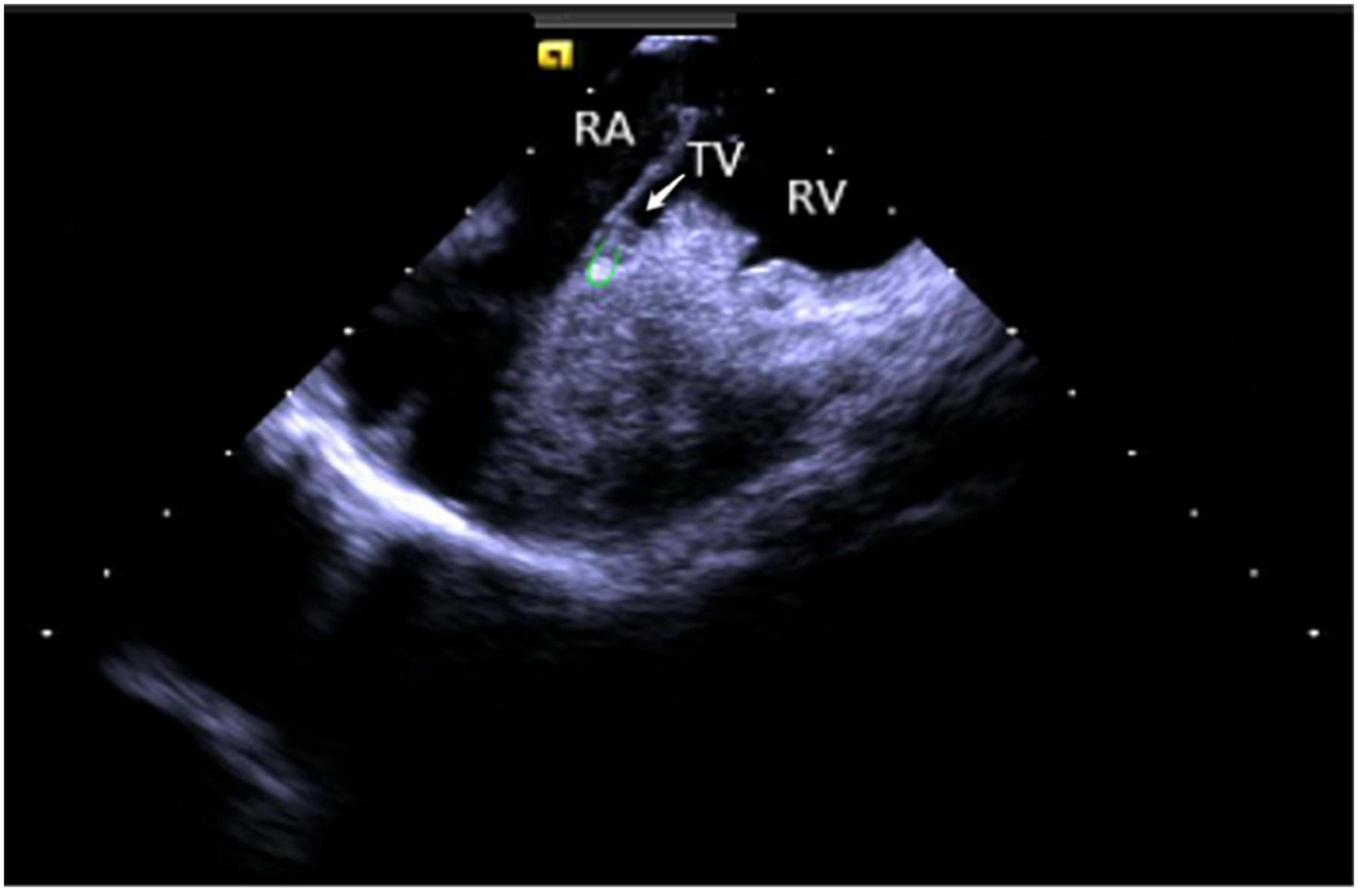

Right ventricular modeling: Based on the HomeView position, the ultrasound sector rotated clockwise toward the RA posterior wall, bending the P curve and directing the catheter into the RV along with the TV orifice. With additional clockwise rotation, the RVOT came into view, along with the long axis of the pulmonary artery, the short axis of the aorta, and the aortic sinus (Figure 3). The catheter was then rotated counterclockwise toward the RV free wall and made an L-bend, thereby showing the RV, LV, moderator band, interventricular septum, and LV anterolateral papillary muscle. Additional downward movement of the catheter to the lowest apical position resulted in the loosening of the L and P bends. Then the catheter was rotated counterclockwise toward the bottom of the RV displaying the moderator band and the papillary muscle of the posterior RV. A continuous counterclockwise rotation toward the RV free wall showed the RV anterior papillary muscle, the free wall of the tricuspid annulus, the subvalvular reflex, and a part of RA (Figure 4). At this point, the RV modeling was complete.

FIGURE 4

Tricuspid annulus subvalvular reflex. RA, right atrium; TV, tricuspid valve; RV, right ventricle.